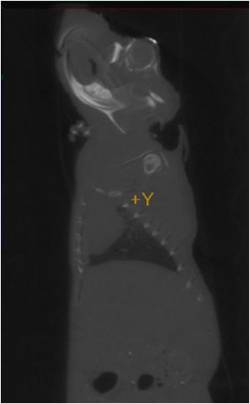

Figure 3. Left and right sagittal CT images of mouse with iodinated liposome injected in left eye vein

Figure 4. Transverse CT image of mouse